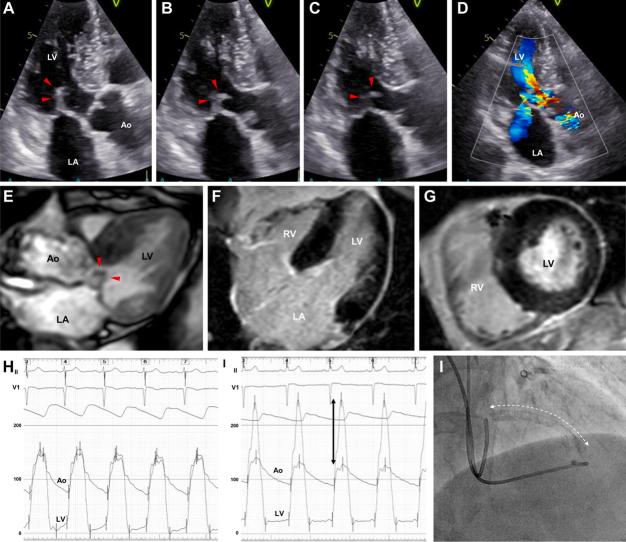

Alcohol septal ablation (ASA) is an effective treatment for drug-refractory hypertrophic obstructive cardiomyopathy (HOCM). However, with prior stent implantation in the left anterior descending artery (LAD), target septal branches can be jailed by a stent, complicating the procedure. A 75-year-old woman with a history of drug-eluting stent implantation was referred for worsening dyspnea. Echocardiography and cardiac catheterization revealed significant left ventricular outflow tract obstruction. Inasmuch as pharmacotherapy failed to control her symptoms, ASA was planned. The target septal branches were jailed by the stent strut. To prevent stent deformation and donor LAD injury during balloon catheter insertion and removal, optical coherence tomography (OCT) was used to guide the guidewire through the appropriate crossing point of the jailed struts, enabling ASA without complications. This is the first report of ASA for stent-jailed septal branches under OCT guidance in drug-refractory HOCM, demonstrating the usefulness of OCT in ASA with stent-jailed target septal branches.

酒精间隔消融术(ASA)是治疗药物难治性肥厚性梗阻性心肌病(HOCM)的一种有效方法。然而,若先前已在左前降支(LAD)植入支架,目标间隔支可能会被支架困住,使手术复杂化。一名有药物洗脱支架植入史的75岁女性因呼吸困难加重前来就诊。超声心动图和心导管检查显示左心室流出道严重梗阻。由于药物治疗未能控制她的症状,遂计划进行ASA。目标间隔支被支架撑条困住。为防止在插入和移除球囊导管期间支架变形以及供体LAD损伤,使用光学相干断层扫描(OCT)引导导丝穿过被困撑条的合适交叉点,从而使ASA顺利完成且无并发症。这是关于在药物难治性HOCM中于OCT引导下对被支架困住的间隔支进行ASA的首例报告,证明了OCT在处理被支架困住的目标间隔支的ASA中的实用性。